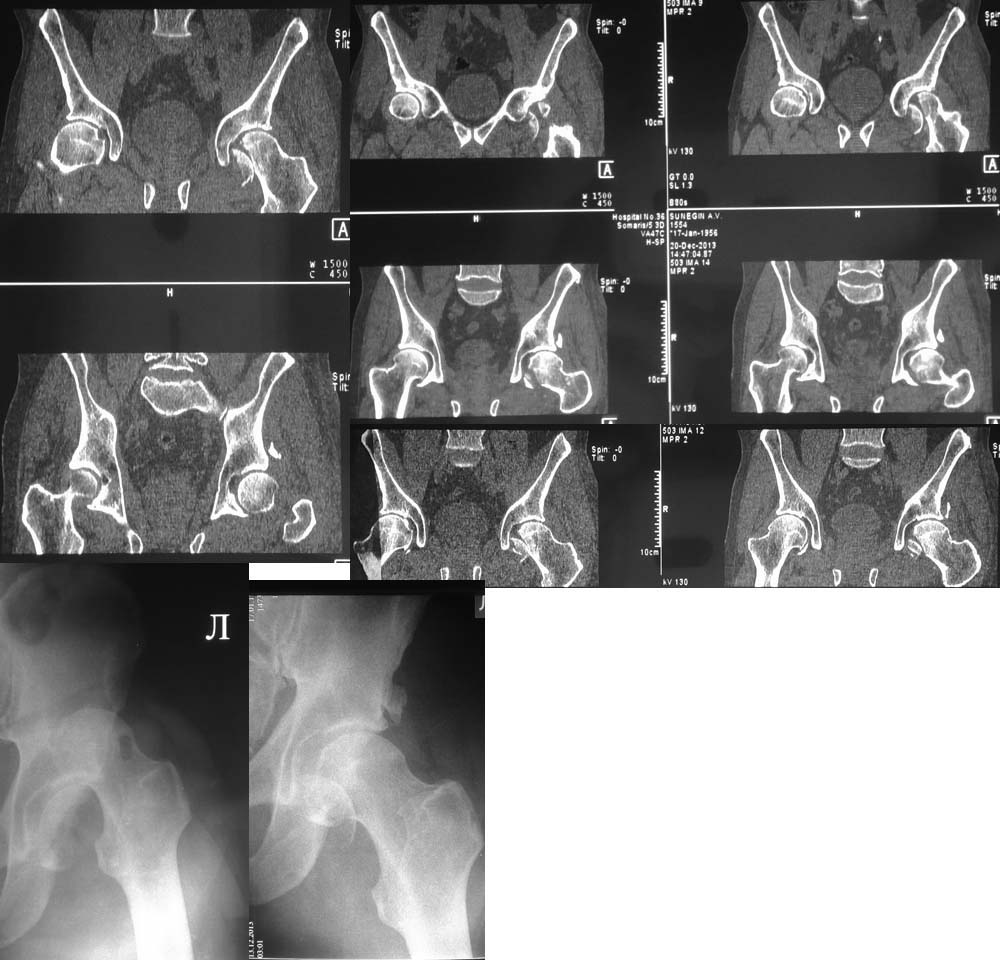

Прошу помочь определиться с тактикой лечения фрагментарного перелома

головки левого бедра Pipkin II, перелом заднего края вертлужной впадины.

Больной С. 1956 г.р. Травма 13.12.13 ДТП, водитель грузового автомобиля.

Первичный вывих бедра. В ЦРБ вправление вывиха, лечение на скелетном

вытяжении. Доставлен в ЦГКБ 24 19.12.13. По представленным

рентгенограмма проведен клинический разбор. Принято решение произвести

остеосинтез фрагмента головки бедра. Проведена компьютерная томография,

данные КТ получены 23.12.12. Прошу помочь определиться с тактикой

лечения. Произвести остеосинтез фрагмента головки бедренной кости,

заднего края вертлужной впадины или тотальное эндопротезирование

тазобедренного сустава.